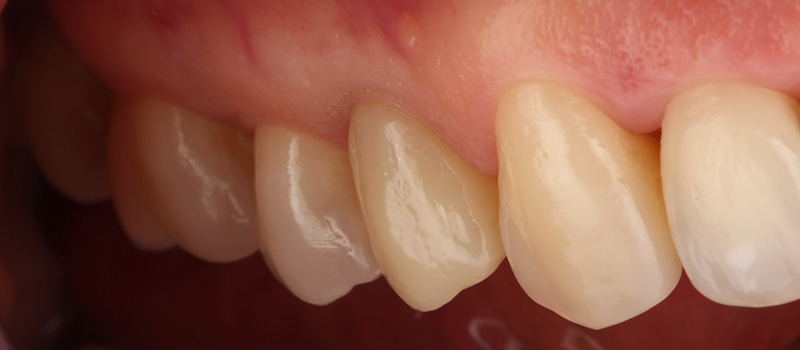

Une patient de 41 ans, consulte au cabinet pour une gêne esthétique et une douleur à la mastication en regard de 14.

Fig. 01 : situation clinique initiale vue vestibulaire, vue latérale et vue occlusale mettant en évidence la fracture du pan palatin de la 14.